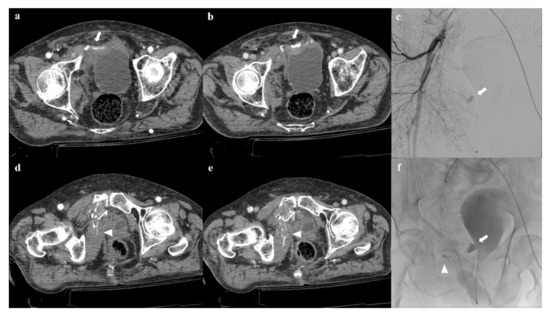

Review

Imaging Review of Pelvic Ring Fractures and Its Complications in High-Energy Trauma

by Edoardo Leone, Andrea Garipoli, Umberto Ripani, Riccardo Maria Lanzetti, Marco Spoliti, Domenico Creta, Carolina Giannace, Antonio Galluzzo, Margherita Trinci and Michele Galluzzo

Pelvic ring fractures are common in high-energy blunt trauma, especially in traffic accidents. These types of injuries have a high rate of morbidity and mortality, due to the common instability of the fractures, and the associated intrapelvic vascular and visceral complications. Computed tomography [...] Read more.

Pelvic ring fractures are common in high-energy blunt trauma, especially in traffic accidents. These types of injuries have a high rate of morbidity and mortality, due to the common instability of the fractures, and the associated intrapelvic vascular and visceral complications. Computed tomography (CT) is the gold standard technique in the evaluation of pelvic trauma because it can quickly and accurately identify pelvic ring fractures, intrapelvic active bleeding, and lesions of other body systems. To properly guide the multidisciplinary management of the polytrauma patient, a classification criterion is mandatory. In this review, we decided to focus on the Young and Burgess classification, because it combines the mechanism and the stability of the fractures, helping to accurately identify injuries and related complications. Full article